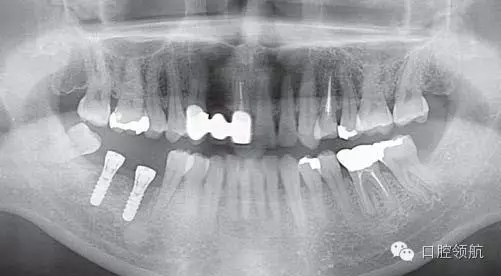

(右下第七、六顆牙)種植體植入術(shù)后(圖1),(右下第七、六顆牙) 拔牙后4個(gè)月植入種植體,埋入時(shí),使用動(dòng)度測(cè)量?jī)x測(cè)量ISQ值為(左下第六顆牙):70∕70;(左下第七顆牙) :75∕75,顯示了良好的初期穩(wěn)定性,6周后又重新測(cè)定了ISQ值為: (左下第六顆牙) :70∕70;(左下第七顆牙):79∕79,遂取印模,制作上部結(jié)構(gòu)(圖2)。因?yàn)榭紤]需要2周的技工制作時(shí)間,所以計(jì)劃在埋入后2個(gè)月安裝最終的上部結(jié)構(gòu)修復(fù)體

圖1 種植體植入后的曲面斷層片。